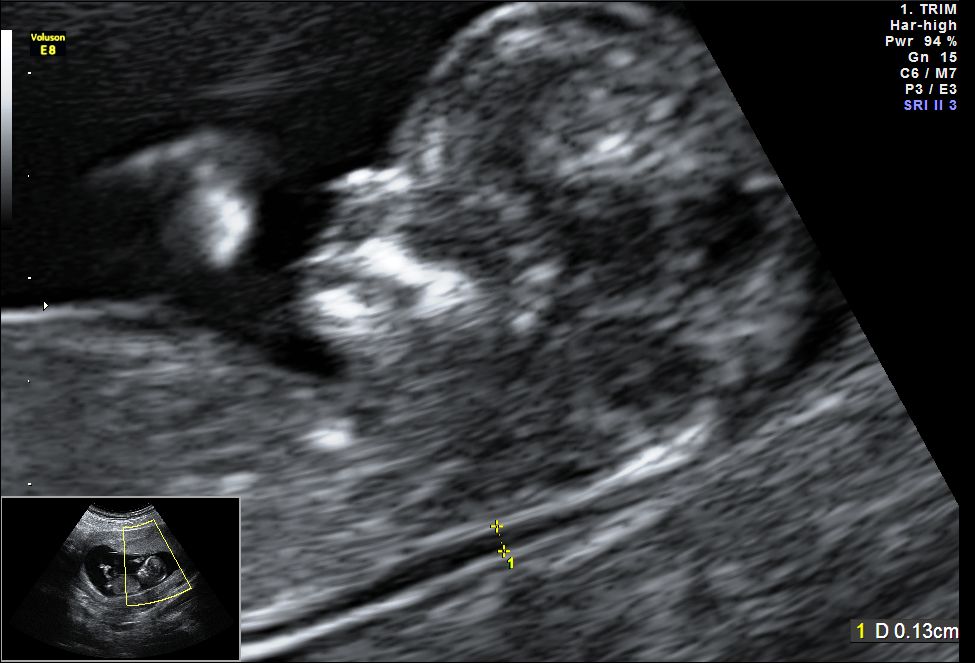

First Trimster Screening (Nuchal translucency, Nasal bone, etc)

This scan is carried out from 11 weeks to 13 weeks and 6 days. The scan is usually performed transabdominally but in a few cases it may be necessary to do the examination transvaginally.

- To estimate risk of Down's syndrome and other chromosomal abnormalities in the fetus : The mother is given an estimate of risk for her fetus having Down syndrome and other chromosomal abnormalities. This is calculated by factoring the age of the mother, levels of free beta hCG and PAPPA in the mother's blood the ultrasound findings ( viz. nuchal translucency measurement, nasal bone, ductus venosus, tricuspid regurgitation and fetal abnormalitites). Parents are explained the significance of these risks and the options for further investigations.